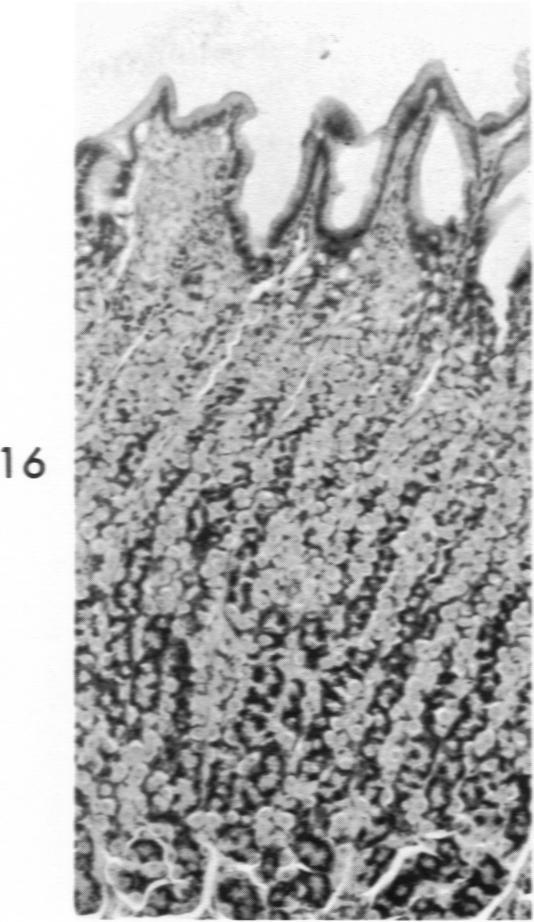

Histochemical and morphologic changes in gastric mucosa of dogs on ulcerogenic regimen.

Am J Pathol. 1969 Jul;56(1):129-51.